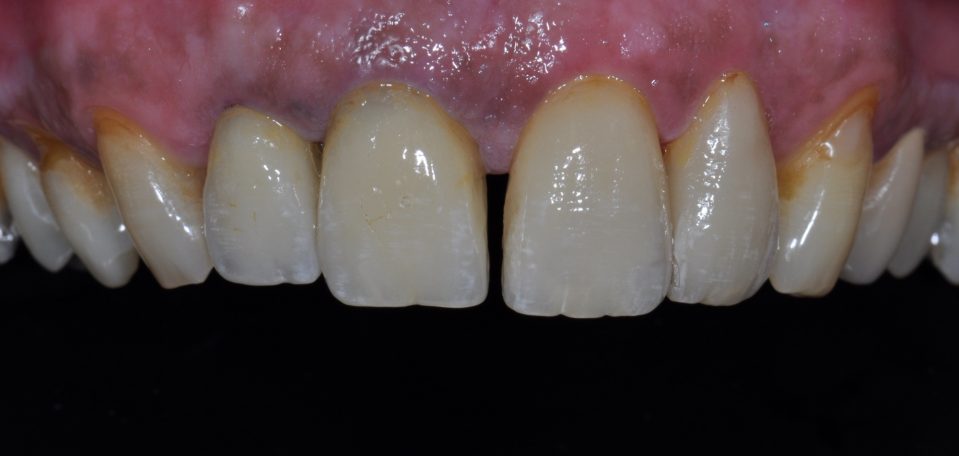

Metallfreie Frontzahnkronen mit individueller keramischer Verblendung.

Frontzahnkronen Oberkiefer neu zur Verbesserung der Ästhetik.